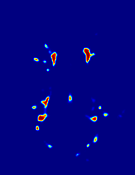

Patch size is another important parameter of the network. In computer vision applications such as object detection, usually a whole 2D image is used as a feature. However, full 3D medical images can not typically be used because of memory limitations. Fig. 4 shows examples of lesion memberships obtained with different sized 2D patches. As the patch sizes increases, the false positives that are mostly observed in the cortex tend to decrease. Fig. 5 shows a plot of Dice and LFPR with various patch sizes, ordered from left to right according to their increasing size. Note that smaller patches ( to ) produced significantly lower Dice and higher LFPR compared to other patches (), as seen from the memberships in Fig. 4. Also some of the highest Dice and lowest LFPR were observed for patches with large in-plane size, i.e., , , and . It was observed in Fig. 5 that there is no significant difference between Dice coefficients for , , or , but LFPR of both and are significantly lower than that of (). We chose as the optimal patch size. Other choices of smaller and patches (not shown) yielded worse results. Note that although training was performed with different patch sizes, the memberships were generated slice by slice, as the trained model consisted only of convolutions and did not need any information about patch sizes.